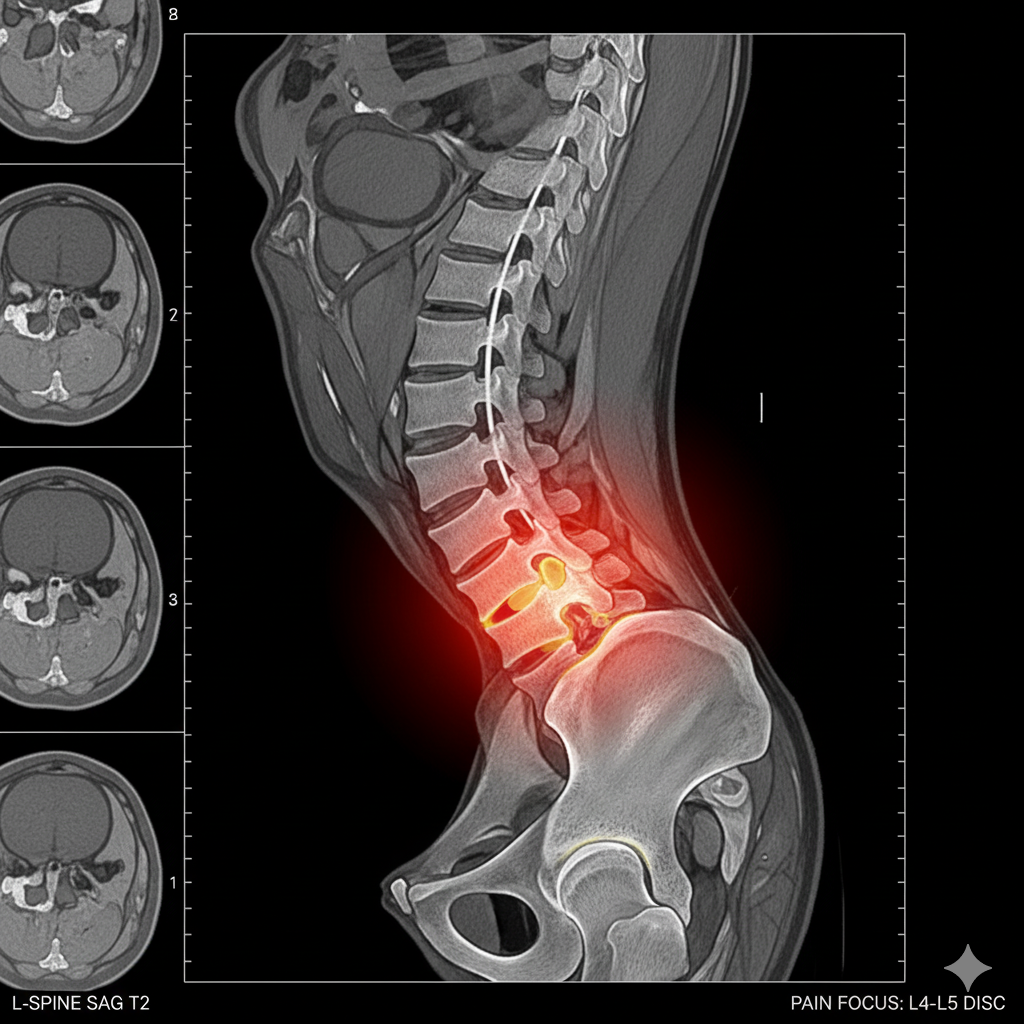

It was devastating — but after reviewing my MRI results, the doctor concluded that I needed spinal surgery to fix what they called “severe disc degeneration and nerve compression.” The inflammation had already started to affect nearby muscles and nerves, and they warned me that waiting too long could cause permanent nerve damage.

I was told that if I didn’t act fast, I could lose mobility in my legs — or even end up unable to walk properly. The idea of losing control over my own body terrified me.